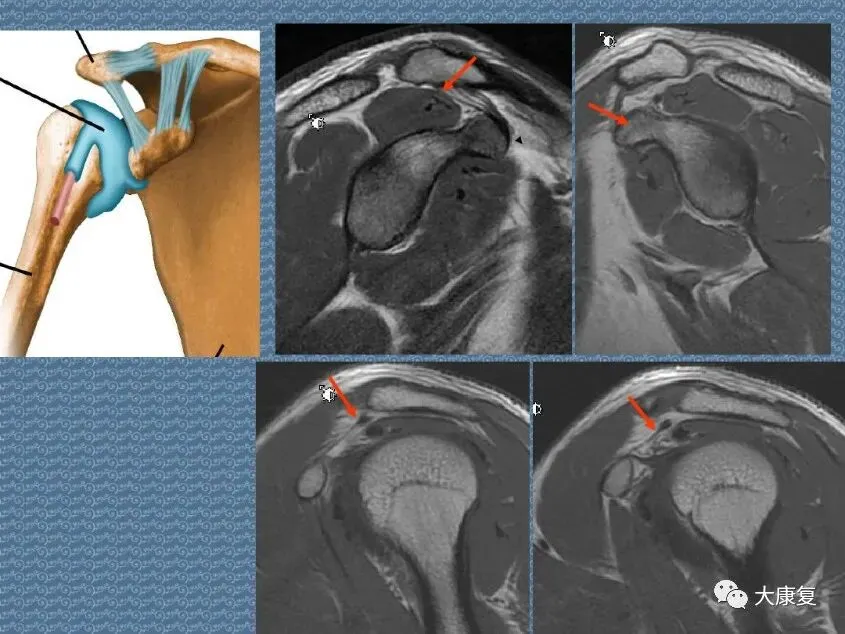

>PPT课件 | 肩关节的解剖结构和特点

PPT课件 | 肩关节的解剖结构和特点